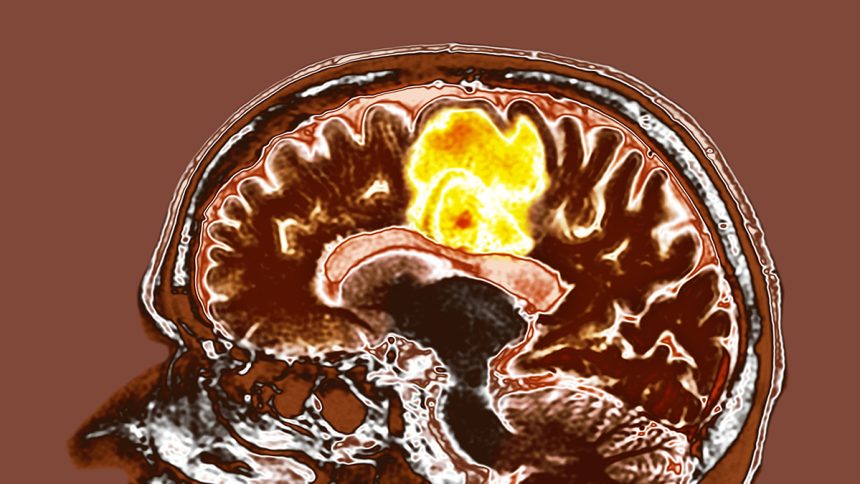

Glioblastoma Study Shows Promising Results with Resveratrol and Copper Supplements

Glioblastoma is a highly aggressive form of cancer, but a recent study testing the effects of resveratrol and copper supplements on glioblastoma tumors has shown encouraging results, potentially opening up new avenues for treatment.